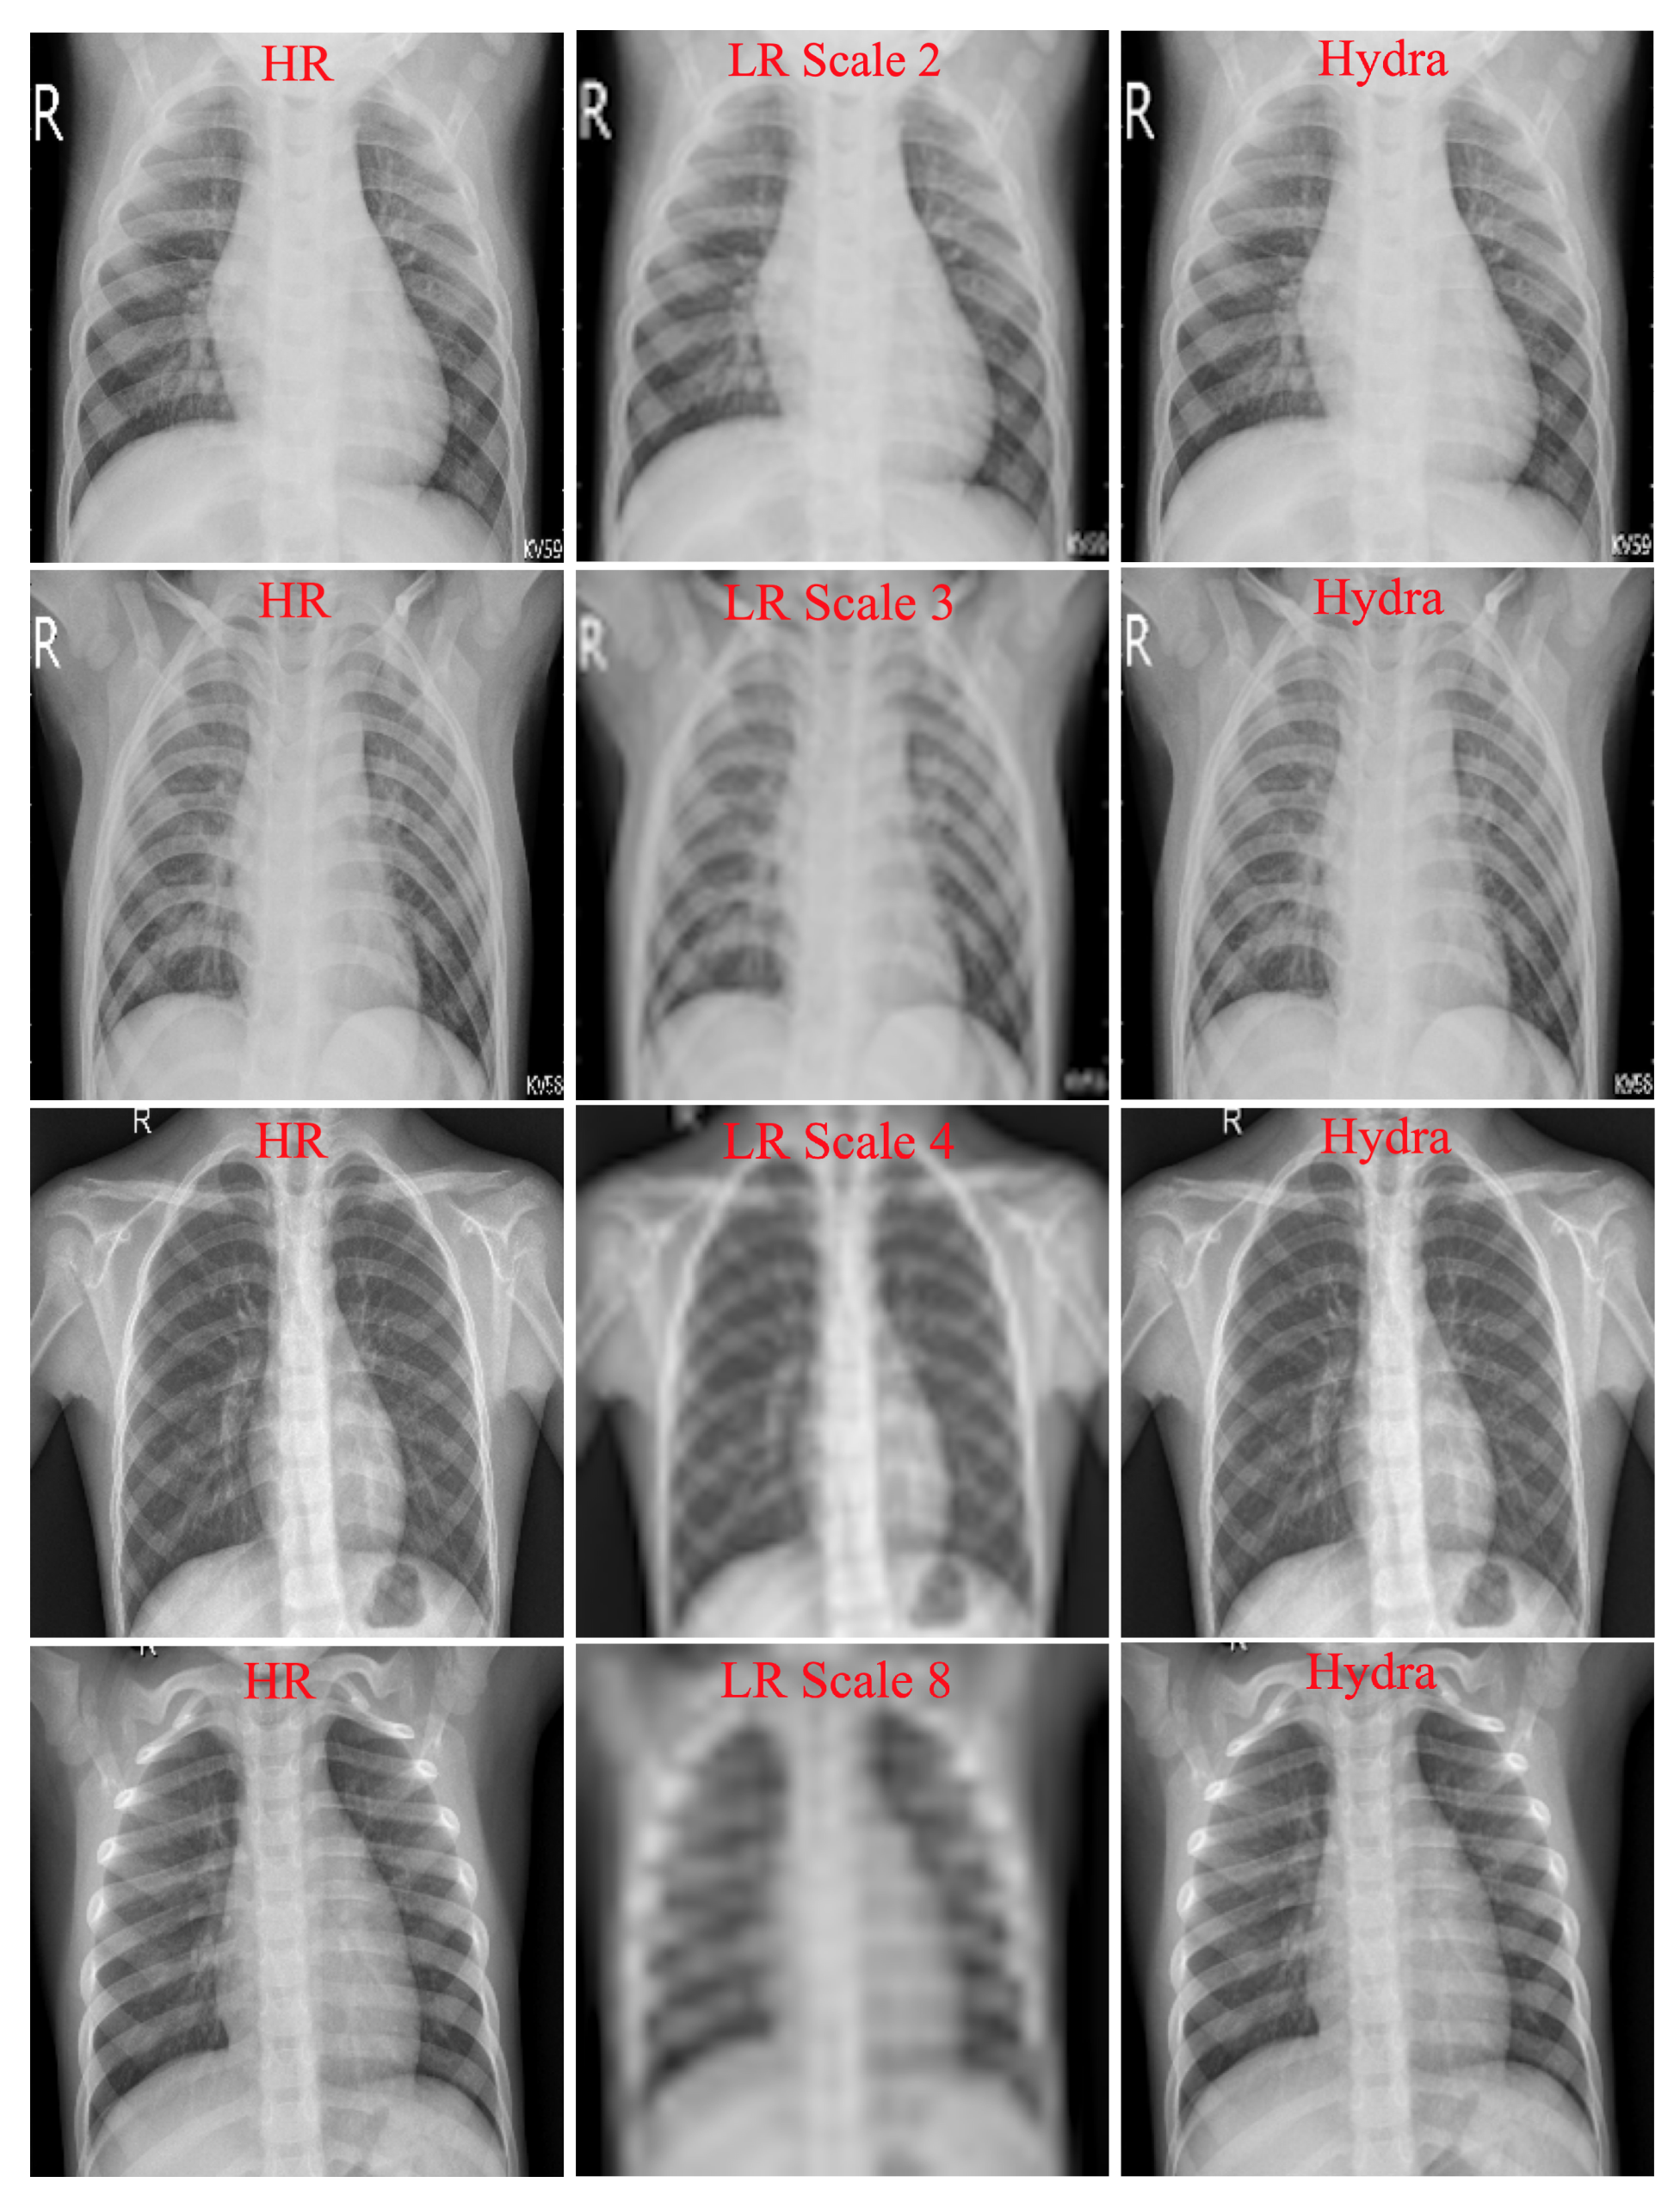

Table 1 shows the results of our customized SISR model and VDSR on the testing set. Because both models are trained on multiple scales (2, 3, 4, and 8) at once, they can be tested with any scale used during training. As can be seen in the table, our SISR model outperformed VDSR in most cases. Recall that VDSR, which contains 20 convolutional layers, is a large model with a relatively large number of parameters as compared to our model (7 layers). These results suggest that our customized SISR can faithfully and efficiently construct HR images. Figure 3 shows examples of SR results with scale factors of 2, 3, 4, and 8 using the Hydra trunk.

Figure 3.

Examples of reconstructed SR images. First column: original HR images. Second column: downsampled input LR images. Third column: reconstructed images obtained using the proposed SISR model (Hydra Trunk).